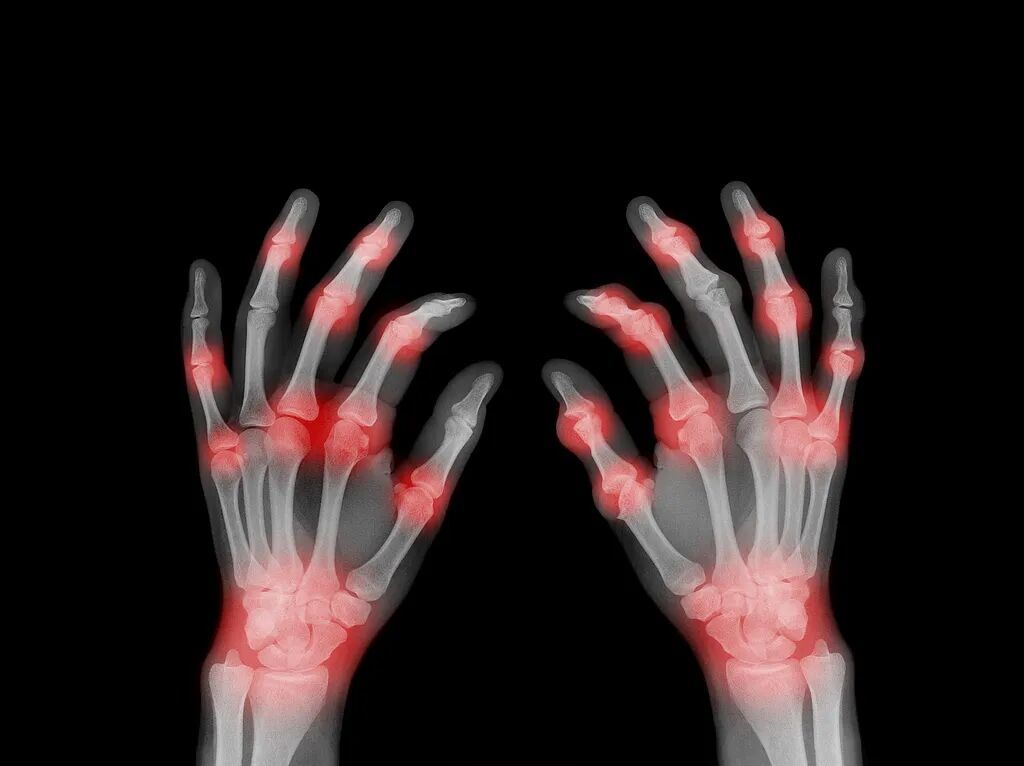

痛风痛风,来去如风。痛风常常在夜间或清晨突然发作,疼痛感像刀割,最常被“袭击”的部位是大拇趾,脚踝、膝盖、手腕、手指等关节也可能中招。发作时,患处会迅速变得红肿,摸上去发烫。

如果长期不控制,血液中过高的尿酸会形成“痛风石”,可能导致关节畸形、活动受限。